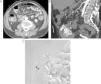

Paciente con anemia ferropénica y estudios endoscópicos previos negativos, que acude por HDB visible. A) La TC muestra extravasación de contraste en un divertículo de yeyuno (flecha). B) Reconstrucción coronal que muestra el divertículo sangrante (flecha gruesa), con extravasación de contraste a la luz intestinal (flechas finas). C) Reconstrucción «volume rendering» que muestra el aporte vascular al divertículo a través de una rama yeyunal (flechas) de la arteria mesentérica superior.

TC en paciente de 75 años con HD crónica de origen indeterminado. A) Reconstrucción MIP axial que muestra múltiples ectasias vasculares en el ciego (flechas) correspondientes a angiodisplasia. B) La reconstrucción MIP coronal muestra las dilataciones vasculares (flechas gruesas) y el retorno venoso precoz de la vena ileocecocólica (flecha fina).